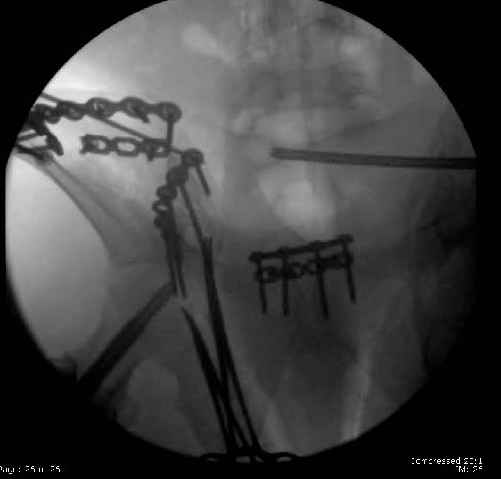

Here are the postop fluoros.

First exposed symphysis & clamped w/Faraboeuf as close to anatomic as possible.

Then extended to R ilioinguinal,really just the lateral window.

Reduced the triangular wedge piece of iliac wing to posterior intact ilium (crescent), held w/k-wire, then used 3-hole push plate to keep from moving, lagged from lat-med w 3.5 screw.

Then 6-hole plate along brim with 1 screw in R sacral ala. Then lagged 2 screws along crest A --> P. finally 10-hole plate along inner aspect of crest. R posterior ilium still a bit stepped off.

Symphysis then 'fine-tuned' & reduced as close as possible to anatomic (but, still with forward rotation of R hemipelvis - or, is it extension?) Accepted that amount of deformity and plated symph

with 4-hole symphyseal plate.

Fluoroed L SI joint and it seemed stable, but wide. So, applied c-clamp to try to squeeze down L SI joint (and note, on the last slide attached, that it's still wide), and got it closer. Single perc Iliosacral screw 40mm thread.

Applied second plate anteriorly on symphysis as I wasn't confident L SI was as stable as it could be and wanted to protect it better.

Thoughts? Thanks for the advice, it's appreciated.